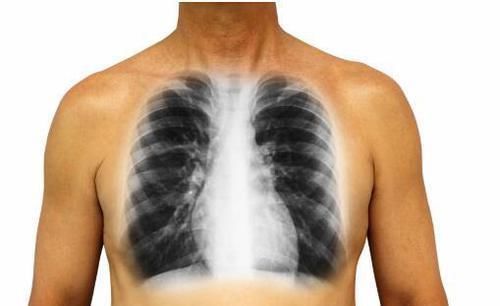

癌细胞|肺癌到了晚期,4个变化很明显,骗不了人,别大意了

肺癌在刚患病的时候可能患者会感觉不疼不痒的,但是等到晚期的时候患者的症状就会变得多起来了,而且患者还会非常的痛苦。其实有很多人都不了解肺癌晚期的症状,到最后也没有采取有效的治疗措施,这样的话患者的痛苦会更严重的,所以接下来就给大家介绍一下肺癌晚期的表现。